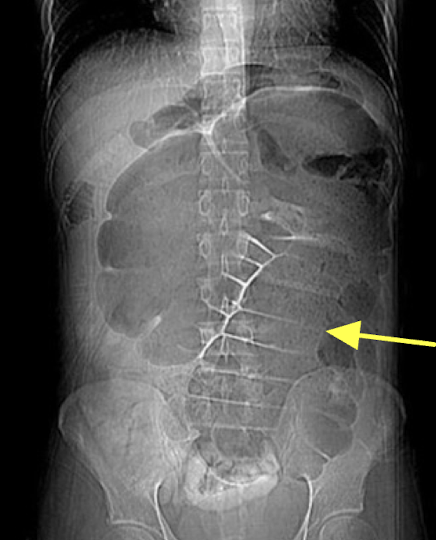

Small bowel obstruction (SBO)

dilation and multiple bubbles, air fluid levels

Abdominal Radiograph

Small bowel obstruction (SBO)

“string of pearls” finding

Abdominal Radiograph